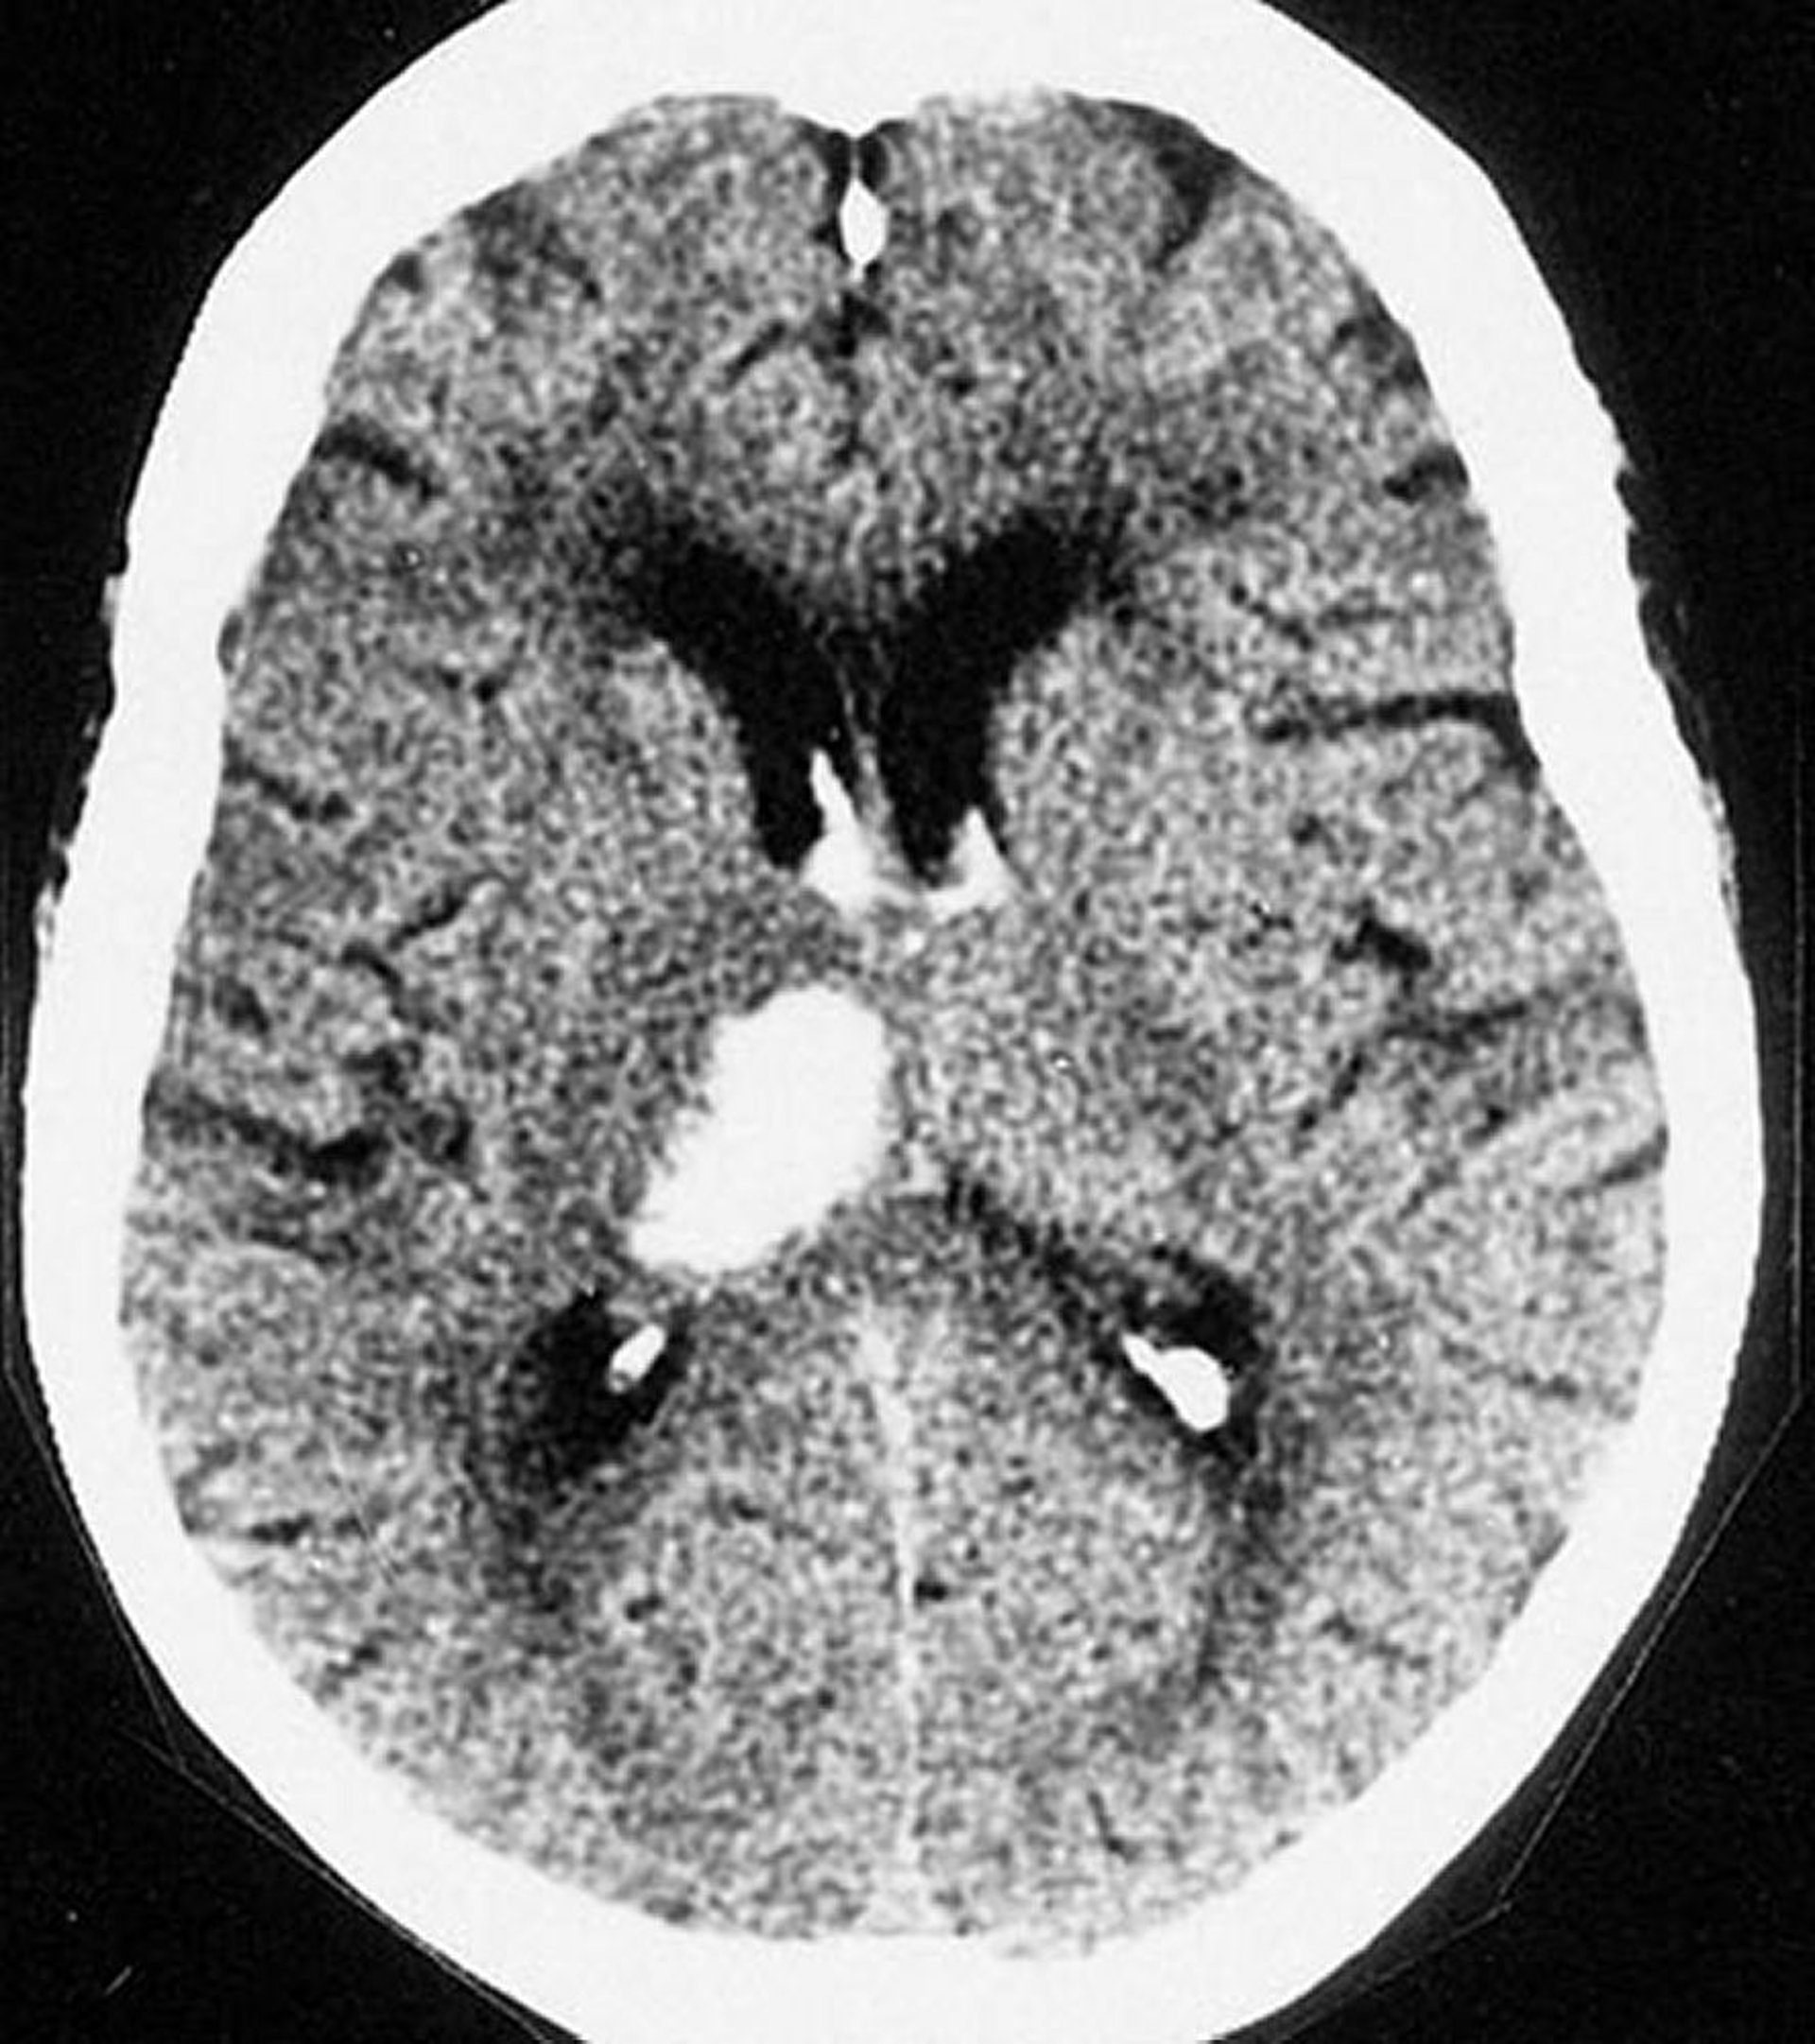

Внутримозговое кровоизлияние в таламус

Этот КТ сканирование показывает кровоизлияние в таламус. Внутримозговое кровоизлияние обычно наблюдаются в таламусе и в базальных ганглиях.

By permission of the publisher. From Furie K, et al. In Atlas of Clinical Neurology. Edited by RN Rosenberg. Philadelphia, Current Medicine, 2002.